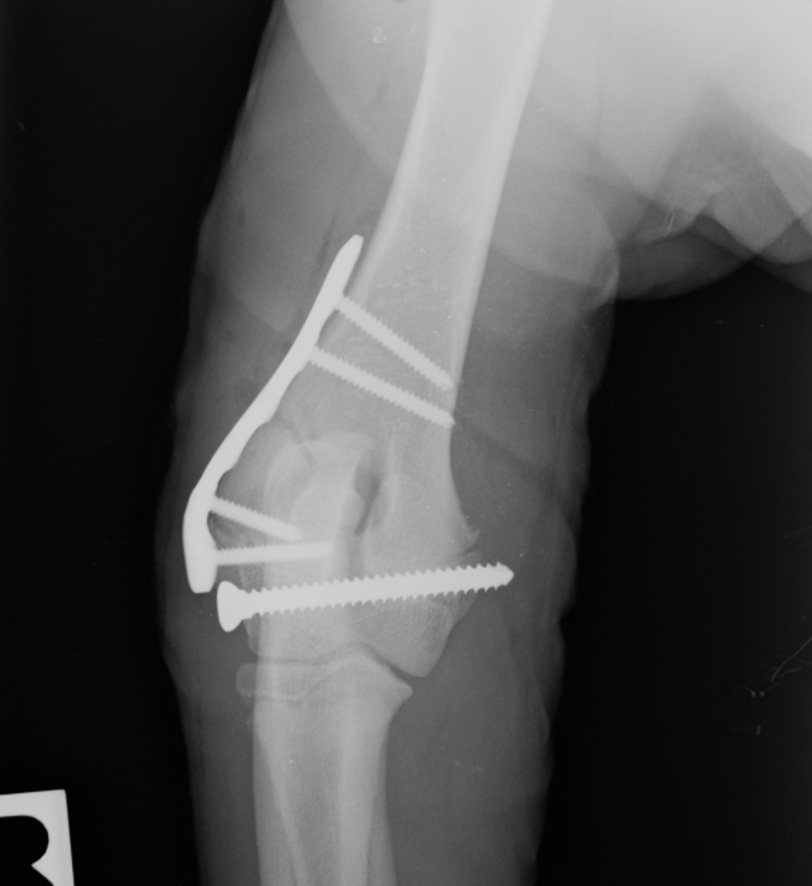

Tibial plateau-leveling osteotomies have become popular techniques for the treatment of canine cranial cruciate ligament disease. This course is designed for the veterinarian who wishes to learn/refine the tibial plateau-leveling osteotomy technique and to understand the major advantages of PAX Polyaxial Locking TPLO Plate System.

Part One of this course is a pre-recorded online lecture that includes a comprehensive discussion aetiopathogenesis, clinical examination, radiographic considerations, TPLO biomechanics, patient selection, complications related to TPLO surgery, pre-surgical planning, instrumentation, surgical technique, and peri/post-operative management.

Part Two of this course is a hands-on workshop. Participants will perform the TPLO technique on a bone model and two canine cadavers under faculty supervision. This lab is only for veterinarians who already have a thorough knowledge of the relevant stifle anatomy, extensive stifle surgery experience, and prior training in bone plating techniques and principles.

This course features two rounds of cadaver work, and each round includes allotted time for pre-op radiographic planning and the instructor’s evaluation of every cadaver’s post-op radiographs. VetRay Technology by Sedecal provides on-site x-ray equipment and support, performing over 150 views at each Securos University 2023 event. They are the world’s largest manufacturer of x-ray equipment and now offer the best selection in digital detector technology. VetRay Technology offers the Digital DX-V which provides HD images within seconds as well as detailed measuring, angle and adjustable circle tools software.